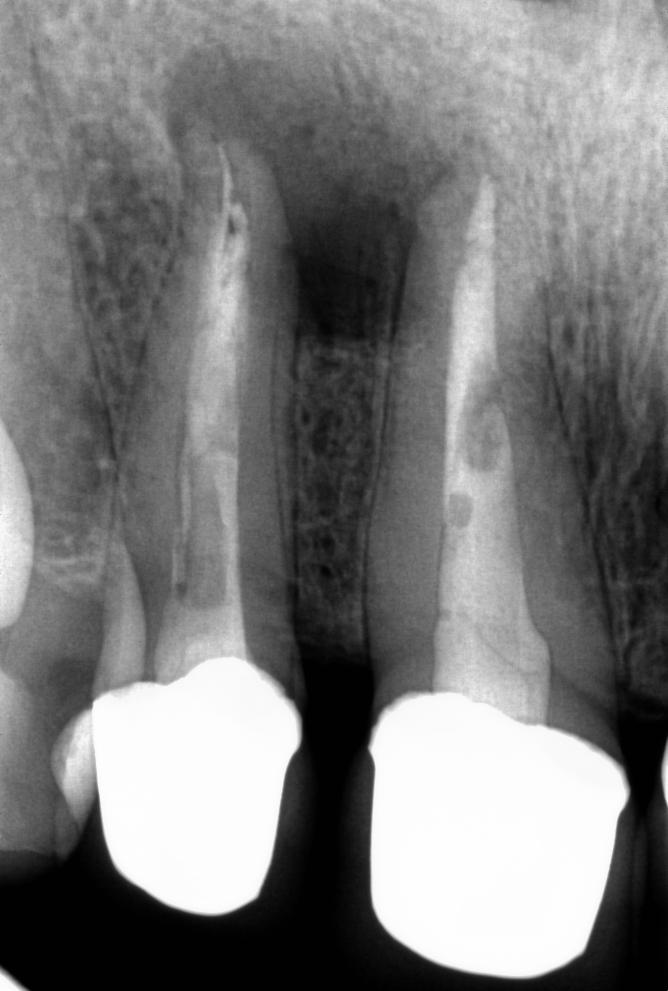

Stan po leczeniu:

Na kontrolnym zdjęciu RTG widoczna jest regeneracja tkanek okołowierzchołkowych i ustąpienie stanu zapalnego. Ząb został uratowany i może nadal pełnić swoją funkcję w jamie ustnej.